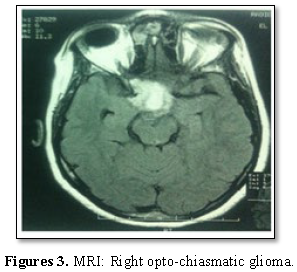

Results: The mean age of patients at the time of diagnosis was 12.67 years (3-27 years) with a slight male predominance (58%). The main functional signs was the decrease of visual acuity (75% of cases), followed by intracranial hypertension syndrome with 58.3%, neurological disorders (hemiplegia and epilepsy) in 33.3% and endocrine signs (amenorrhea) in 16.7% of cases. Tumors were solid in 25% of cases and Solido-cystic in 75% of cases on MRI. Surgical removal was partial in 11 patients (92%) and total in 1 patient whose lesion affected only the optic nerve. Visual improvement was noted in 9 patients (75%), no neurological worsening or operative death was reported. Only one patient had presented 27 months after surgery, epilepsy leading to the death.

The 12 patients were operated through fronto-pterional or sub-frontal approach. Surgical removal was partial in 11 patients with chiasmatic and opto-chiasmatic glioma (92%). One patient whose lesion affected only the left optic nerve had total resection associated to its sacrifice. All tumors were pilocytic astrocytomas (grade I WHO classification). No postoperative complications were noted. Two patients received radiotherapy (1 preoperatively and 1 postoperatively). Two patients received chemotherapy postoperatively. Visual improvement was reported in 9 patients (75%). No visual or neurological worsening was described. Only one patient had presented 27 months after surgery, epilepsy leading to the death. The results of the follow-up are illustrated in Table 1.

Optic pathway gliomas represents 0.5 to 5.1% of all intracranial tumors [3,7] but 65% of primary tumors in the optic nerve [8]. This frequency is higher in children with neurofibromatosis type 1 (up to 30%) [4]. The average age was 12.67 years. In comparison, one of the most comprehensive studies published by DUTTON about 2297 cases; the average age was 8.8 years of which 90% of cases were under 20 years. The mean time to diagnosis is 3 years for our patients with optic nerve glioma, 5 months for those with chiasmal glioma and 14.8 months for those with opto-chiasmatic involvement [9]. In the BATAINI series [10], the average time between the first symptoms and diagnosis is estimated at 14.6 months. This delay varies according to the nature of the clinical signs and the tumor topography. According to Appeleton [11], only exophthalmia allows early diagnosis because it is easily recognizable. Our series reports a male predominance. This is not corroborated in the various series, which do not find either predominance of sex [12] or on the contrary, a slight female predominance [13]. Exophthalmia, visual loss and strabismus are the three most common symptoms [6]. The decrease of the visual acuity is the first revealing sign. It is usually a slow, gradual decrease that can be uni or bilateral [11,14]. When it is present, it is often very severe. In fact, 80% of Optic pathway gliomas have a low visual acuity less than 1/10 according to RUSH [15] and 67% of patients counted only the fingers, in the JAKOBIEC series [16]. It should be noted that visual acuity is not always quantifiable in very young children because of their lack of “cooperation” and it is a sign that is not constant. Papilledema was present in 2 cases (17%) and optic atrophy was noted in 2 others. Wright [17] notes in his study that papilledema is mainly present in evolutionary tumors. Oculomotor disorders are infrequent and occur in only 17.6% of optic pathway gliomas [18]. However intracranial hypertension (ICH) is the most common tell-tale sign of optic pathway gliomas by hydrocephalus [19]. It was noted in 7 of our patients (58%). ICH is a pejorative sign as reported by a recent study which shows that patients with ICH have a low survival rate compared to patients who do not have this symptom [6]. It may appear in the course of evolution and is related to the posterior chiasmatic extension, blocking the third ventricle and Monro's hole. Other neurological signs (hemiplegia, epilepsy, walking disorder, balance disorder) may sometimes exist [14]. Their presence is a poor prognosis factor. On the other hand, opto-chiasmatic gliomas may be responsible for endocrine disorders by hypothalamic extension (early puberty, Russel syndrome, diabetes insipidus or anterior pituitary insufficiency) [20]. Lund [21] considers that the use of visual evoked response is more interesting than neuroradiological techniques for the detection of optic pathway gliomas, as they do not require sedation and can play an important role in monitoring in order to evaluate the visual function, residual visualization after surgery or for children for whom no treatment has been recommended. MRI allows a better diagnosisto monitor tumor progression and treatment response. Regarding the tumor localization, it is difficult to obtain reliable statistics. However, it appears that 25% of gliomas remain confined to the optic nerve and 75% reach the chiasm while extension to the optic nerve head and intraocular structures is rare [24]. Despite extensive literature, the treatment of optic pathway gliomas is controversial because of too small series, too short follow-ups, and the heterogeneity of the groups. Similarly, the unpredictable evolution of these tumors justifies the different therapeutic options proposed by different authors, ranging from simple observation to radiotherapy, chemotherapy, surgical resection and/or the combination of these different means [2,6,12,13]. The current approach is to start treatment when visual impairment is evident and/or tumor enlargement on imaging. In case of optic nerve glioma, the surgery must be as radical as possible and offer a definitive cure [23]. The decision to resect the optic nerve should be made in case of blindness and when the tumor is responsible for severe exophthalmos. Otherwise, in case of preserved or partially preserved vision or moderate exophthalmia, the “wait and see” policy should be adopted first [6]. The size and extent of the tumor influences the surgical management.When the tumor affects the optic chiasm, with an anterior extension to the optic nerves or posterior to the hypothalamus, the role of the surgery is not well clarified. These lesions respond better to radiotherapy [22]. To avoid worsening of visual function, a limited biopsy before radiotherapy is the best choice [6,27]. In our series, 11 patients underwent partial excision of the tumor with a visual improvement in 9 patients (75%). In addition, surgery can be indicated in case of differential diagnosis with others sellar tumors as craniopharyngioma. In case of surgery, blindness threatens 66.6% of children treated by partial resection [18,23]. Immediate postoperative complications are poorly documented in the literature but their frequency tends to decrease due to the advent of new neurosurgical techniques [24]. We did not note any of them in our series. Most of optic pathway gliomas are benign pilocytic and pilomyxoid astrocytomas [3].The role of radiotherapy is highly controversial and its usefulness remains to be proven. Some series report an improvement in visual acuity after radiotherapy [15]. Pierce [17], obtained 91% of good visual results after radiotherapy. However, other studies showed no improvement in survival or visual acuity and some researchers have even warned of the dangerous effects of radiation in children [25,26]. It is used at doses ranging from 4500 cGy for tumors limited to chiasma and 5500-6000 cGy for tumors invading the hypothalamus [27]. Chemotherapy, by offering a first-line treatment, may have a therapeutic effect, at least by delaying the indication of radiotherapy. Regarding the role of chemotherapy, Petronio [28] reports that all those for whom the tumor responded to chemotherapy had an improvement or stabilization of visual acuity. But other authors report that chemotherapy has not yet sufficient evidence of efficacy to be proposed as the first therapeutic choice [29].